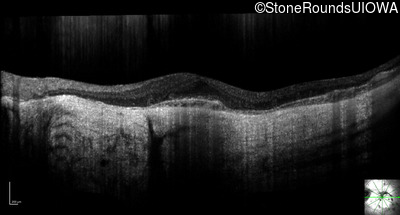

Optical Coherence Tomography - Left - 20/20 -1

Exemplar / OCT Stack

OCT Stack

Infrared Fundus Photograph - Right - 20/100 -2